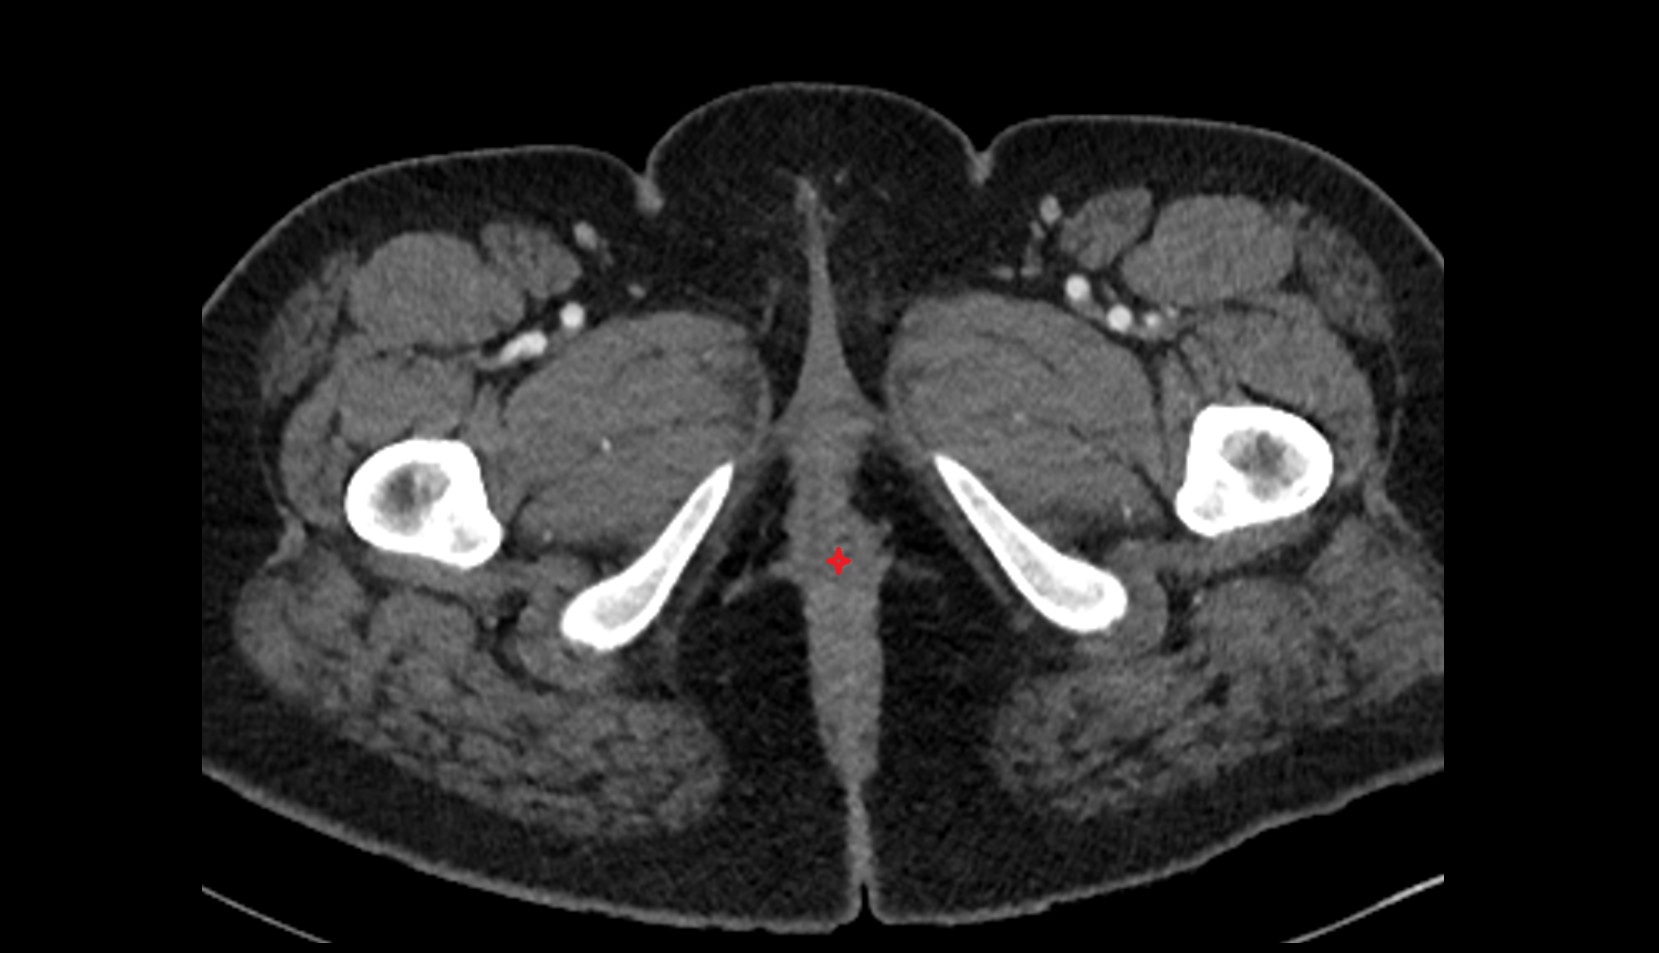

- Testis

- Tunica albuginea (penis)

- Tunica albuginea of testis

- Septum of scrotum

- Skin of scrotum

- External spermatic fascia

- Cremaster fascia

- Internal spermatic fascia

- Parietal tunica vaginalis

- Lobule of testis

- Mediastinum testis

- Visceral tunica vaginalis

- Scrotal fluid

- Septum of testis